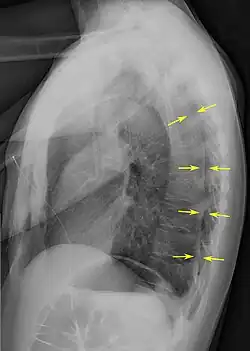

Una radiografía realizada en proyección postero-anterior (de atrás hacia delante) y durante la inspiración máxima constituye la forma de diagnóstico más frecuente.[38] Las imágenes realizadas en espiración, al contrario, no poseen valor diagnóstico significativo,[20] aunque pueden resultar útiles cuando existe una alta sospecha de neumotórax, pero la radiografía en inspiración aparece normal.[39] Si este es el caso, también pueden realizarse radiografías de proyección lateral, aunque esta práctica no se realiza con frecuencia.[20][31]

-

radiografía anteroposterior que muestra un neumotórax de reducido tamaño en el pulmón izquierdo, causado por una punción -

Radiografía lateral en inspiración, que muestra el neumotórax en la parte posterior -

Radiografía anteroposterior en espiración en la que también puede observarse el neumotórax

A veces puede darse una desviación del mediastino hacia el lado contrario en el que se halla el neumotórax debido a las diferencias de presión que crea esta patología. La presencia de esta desviación no implica la existencia de un neumotórax a tensión, que habitualmente se diagnostica a través de signos de gravedad como hipoxia severa y choque obstructivo.[30]

El tamaño del neumotórax (es decir, la cantidad que este ocupa en la cavidad pleural) puede determinarse midiendo la distancia entre la caja torácica y el borde del pulmón. Esto es de relevancia para el tratamiento, ya que los neumotórax de menor tamaño a menudo poseen un enfoque terapéutico distinto. Una distancia de dos centímetros significa que el neumotórax ocupa un 50 % del hemitórax.[20] Las guías de práctica clínica afirman que esta medida debe darse a partir del hilio pulmonar, con un umbral de referencia de dos centímetros para indicar la presencia de un neumotórax de menor o mayor tamaño. La medida también puede realizarse a partir del ápice pulmonar, y en este caso el umbral es de tres centímetros,[40] aunque esta forma de medición puede hacer pensar que el tamaño del neumotórax es mayor si este se encuentra concentrado en la parte superior de la caja torácica.[20][31] Aun teniendo en cuenta esto, estos métodos de medida no poseen una correlación perfecta con el tamaño del neumotórax y, aunque el TAC ofrece imágenes más precisas en este sentido, se desaconseja su uso en estas situaciones clínicas.[20]

No todos los neumotórax son uniformes; algunos ocupan solamente un pequeño espacio en un espacio particular de la cavidad pleural.[20] A veces, pueden hallarse pequeñas cantidades de líquido en la radiografía (hidroneumotórax), que puede estar constituido por sangre (hemoneumotórax).[30] En algunos casos la única manifestación de estos que se da en la radiografía es el signo del surco profundo, por el cual se da un aumento del espacio entre la caja torácica y el diafragma por la presencia de líquido.[35]